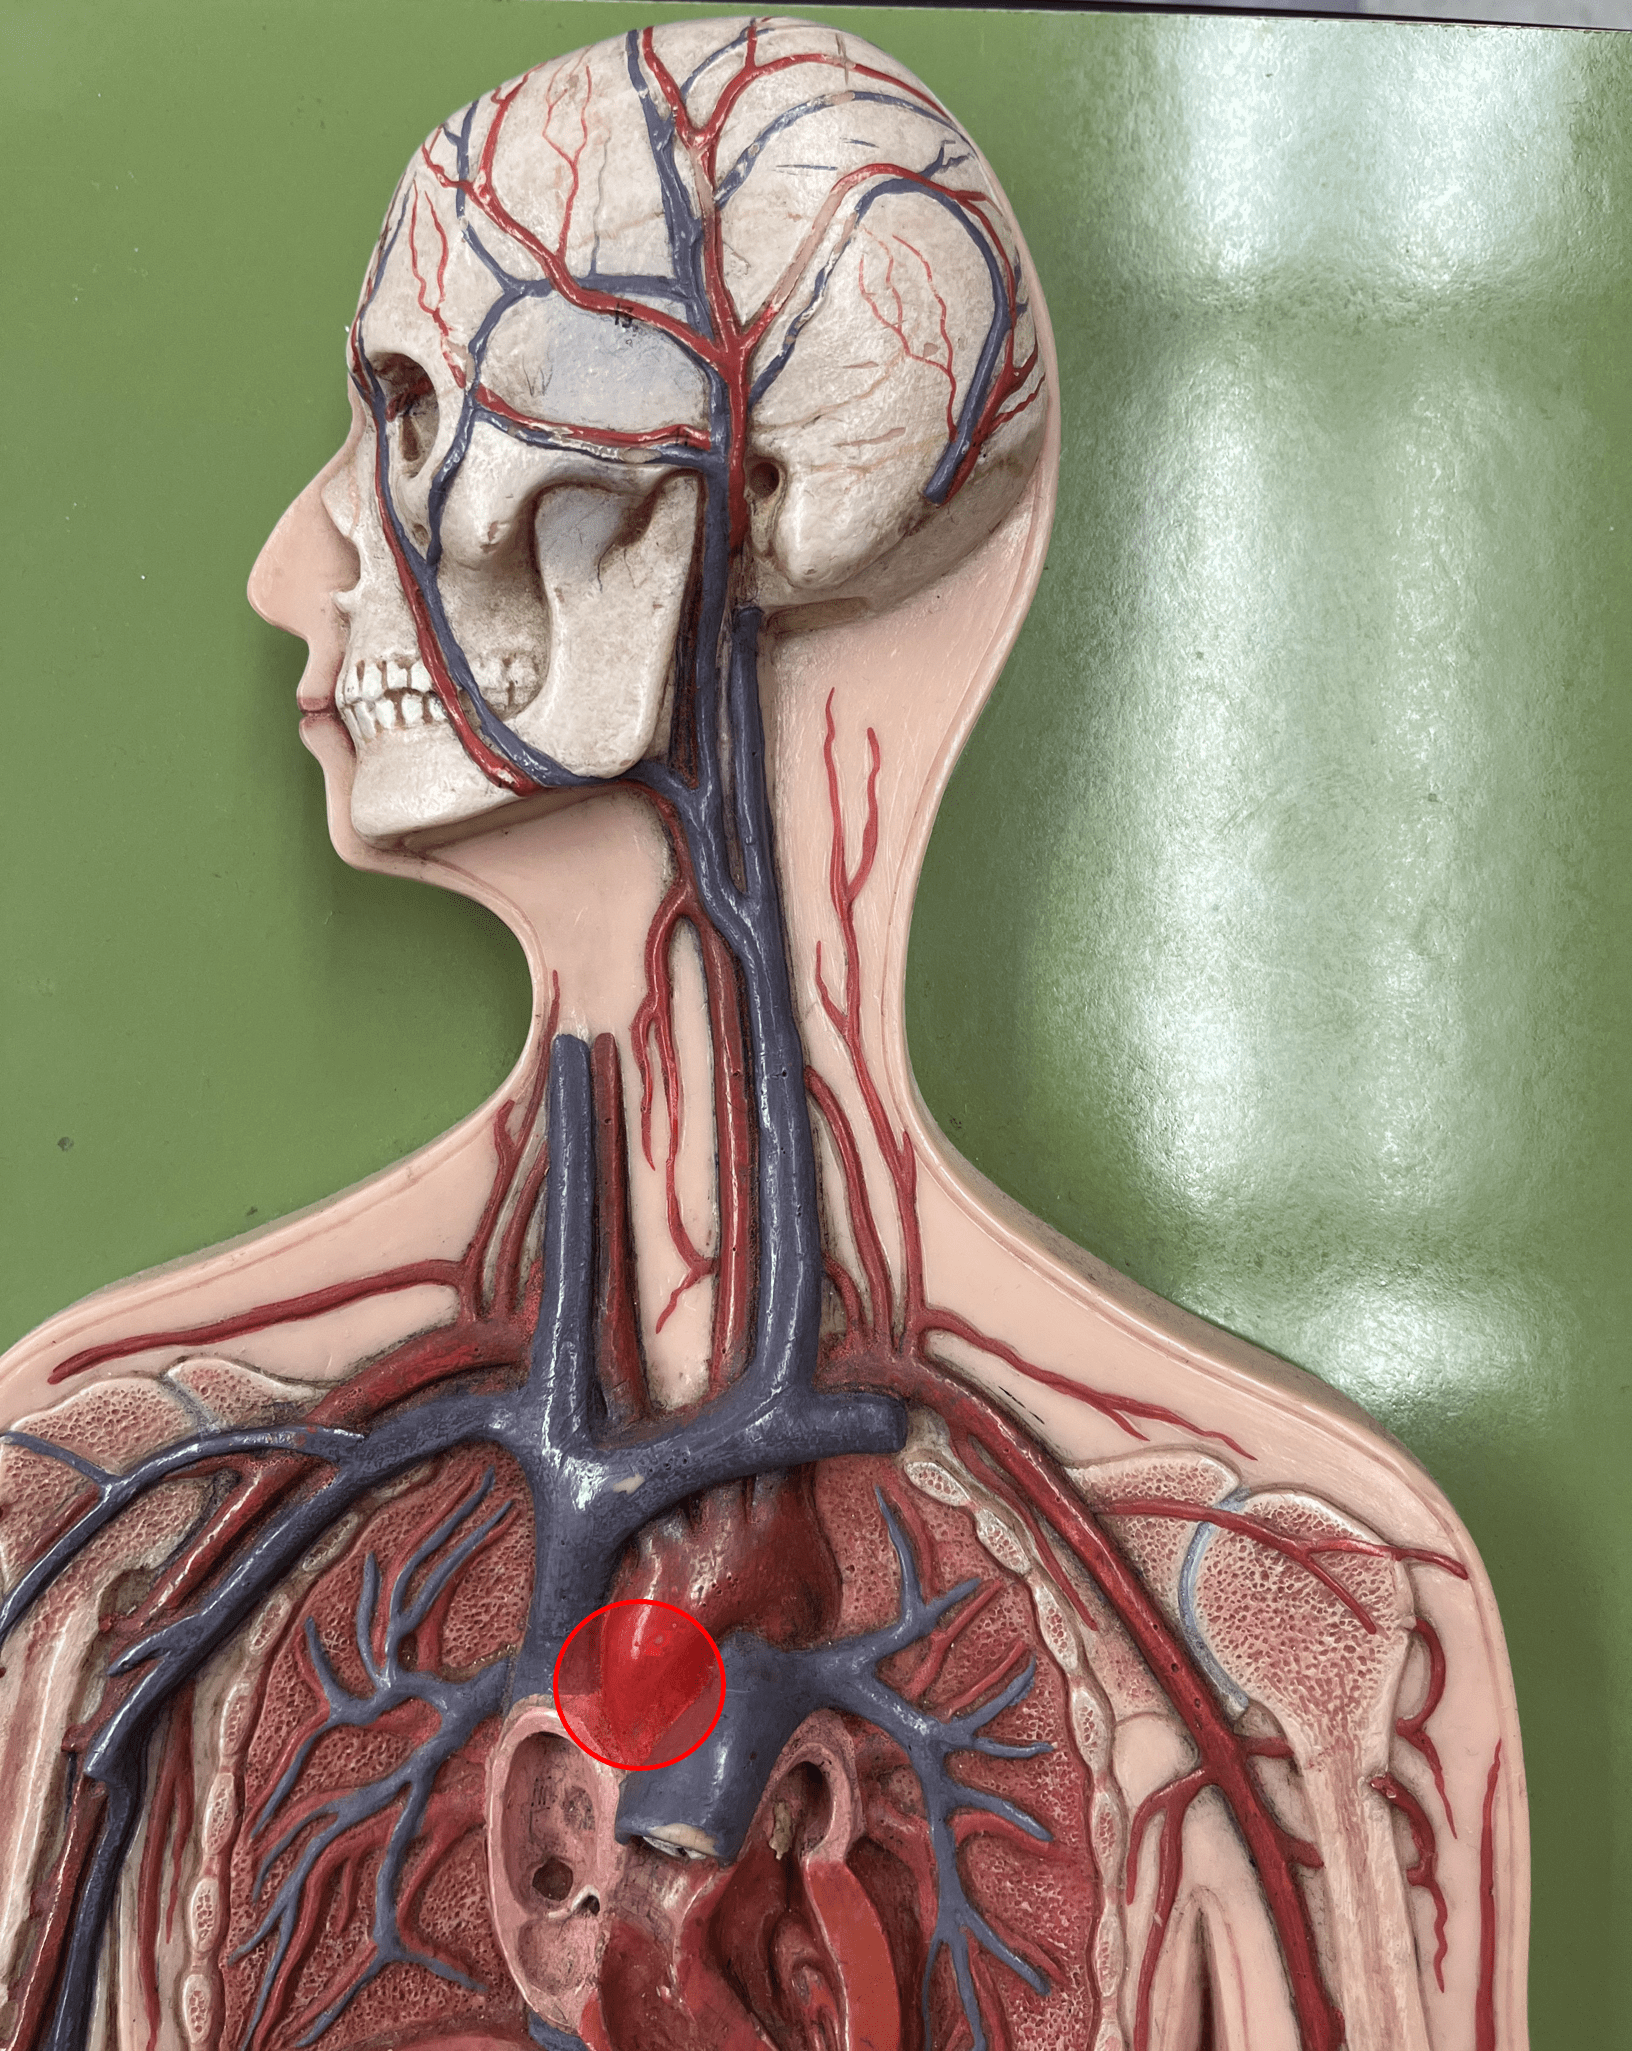

brachiocephalic trunk

• An artery of the thorax.

• Originates from the aortic arch.

• Supplies its branches: the R. subclavian and R. common carotid arteries.

• Originates from the aortic arch.

• Supplies its branches: the R. subclavian and R. common carotid arteries.

ascending aorta

• An artery of the thorax.

• Originates from the left ventricle of the heart.

• Supplies its branches.

• Originates from the left ventricle of the heart.

• Supplies its branches.

aortic arch

• An artery of the thorax.

• Originates as the continuation of the ascending aorta.

• Supplies its branches: the brachiocephalic trunk, L. subclavian artery, and L. common carotid artery.

• Originates as the continuation of the ascending aorta.

• Supplies its branches: the brachiocephalic trunk, L. subclavian artery, and L. common carotid artery.

subclavian artery

• An artery of the thorax.

• Originates from the brachiocephalic trunk (R.) or the aortic arch (L.).

• Supplies its branches.

• Originates from the brachiocephalic trunk (R.) or the aortic arch (L.).

• Supplies its branches.